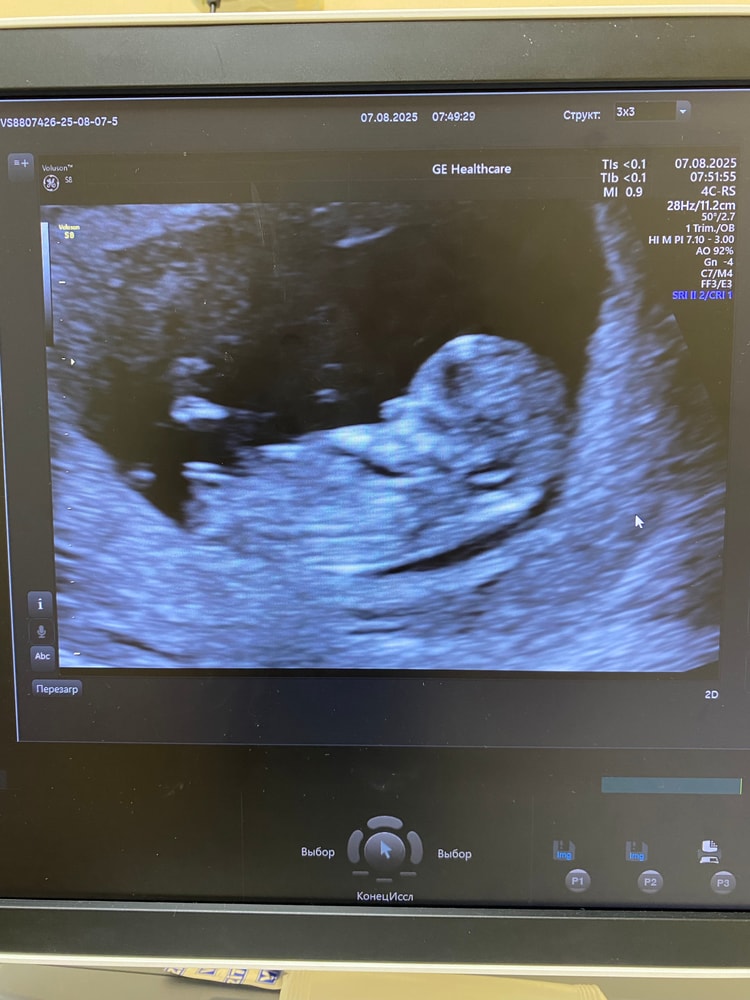

СкринингУра! Закончился один из самых страшных периодов, сегодня была на скрининге. Врач очень классная попалась, все показывала, рассказывала. По узи все хорошо, носик на месте, твп в норме, креветка уже 52 мм❤️

Сказала 90% пацан😁